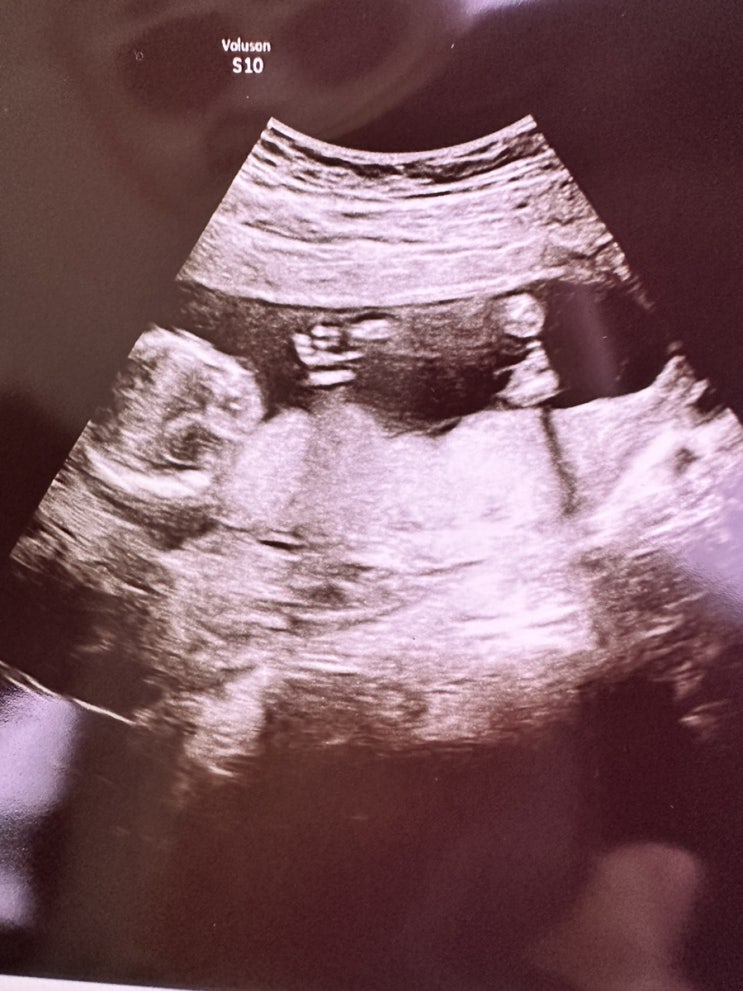

임신 병원비, 니프티검사비용, 임신초기 할일, 아기용품 한번에 정리했어요 :)

저는 펫블로거지만 임산부이기도 하기에 저의 기록용 + 정보제공용으로 한번 포스팅해 볼게요! 내용은 임신...

2달간의 일기 행복한 일상 :)

진짜 오랜만에 블로그 포스팅하는 것 같아요! 그동안 이렇게 오래 쉰 적이 없었는데 뱃속에 꼬물이가 와줘...